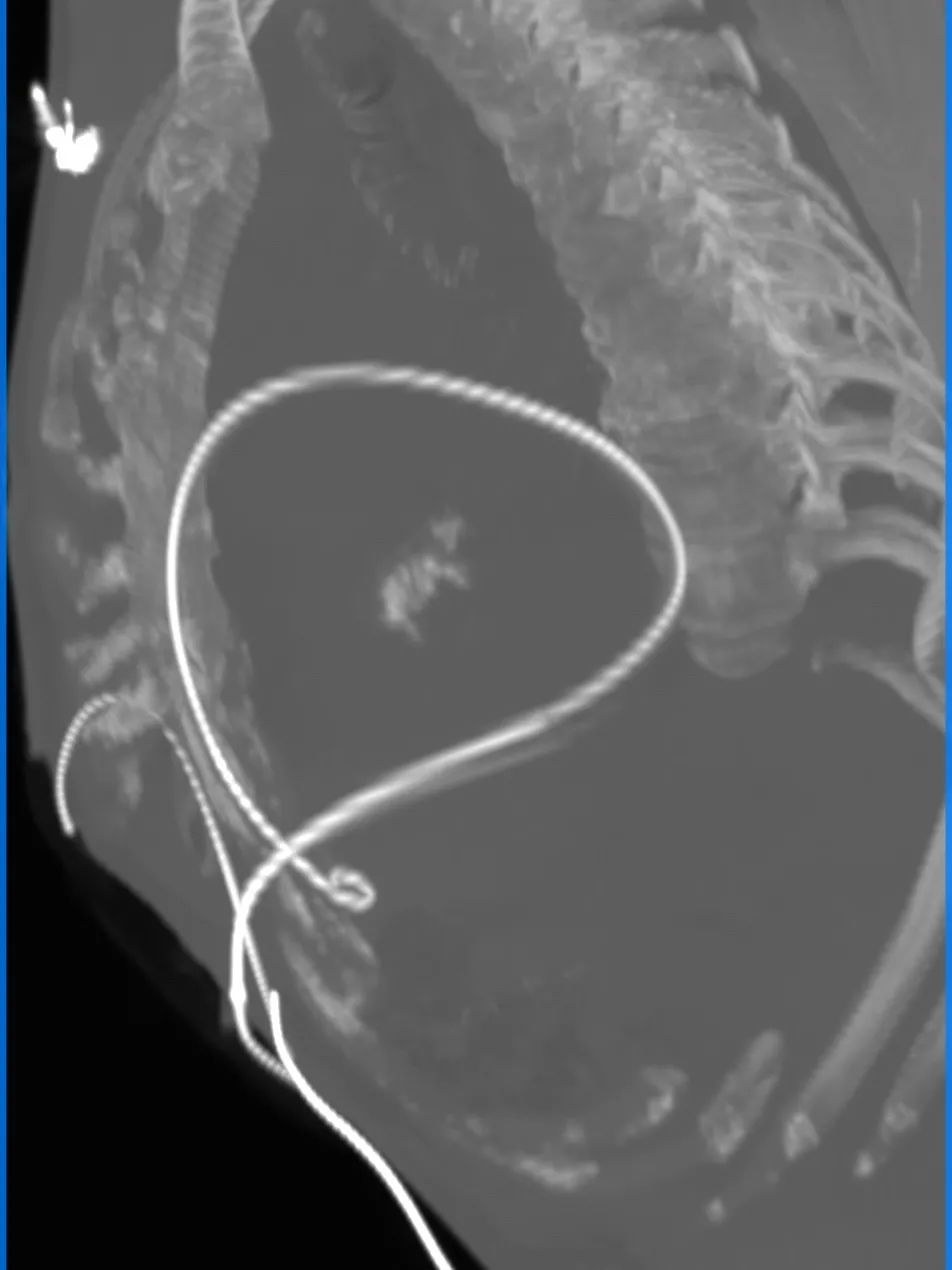

3D入路全程

R/L股动脉分叉位置

主入路条件